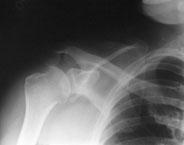

Ein 44-jähriger Patient ist auf dem ersten Eis des Winters ausgerutscht und auf die rechte Schulter gestürzt.

Er klagt über starke Schmerzen im Bereich der rechten Schulter und ein Instabilitätsgefühl im Gelenk. Die Beweglichkeit des Arms ist aufgrund der Schmerzen eingeschränkt, Durchlutung und Sensibilität sind normal.